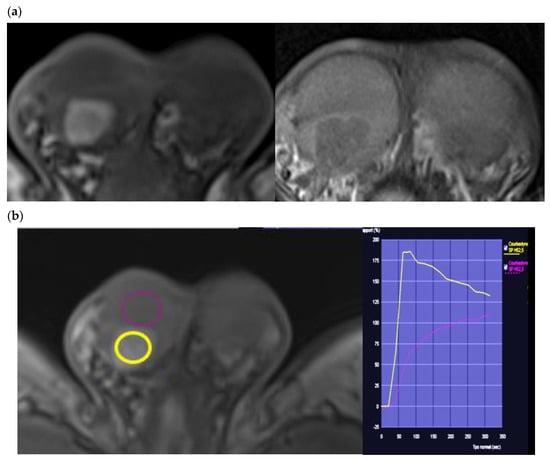

4.3. Dynamic Contrast-Enhanced MRI